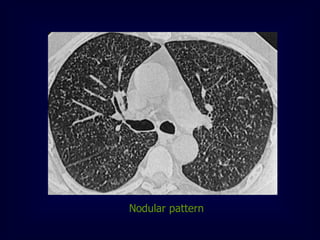

Nodular pattern

[ multiple rounded opacities 1-10mm]

c. Nodular pattern

 A nodular pattern consists of multiple round opacities,

generally ranging in diameter from 1 mm to 1 cm

 Nodular opacities may be described as miliary (1 to 2 mm,

the size of millet seeds), small, medium, or large, as the

diameter of the opacities increases

 A nodular pattern, especially with predominant

distribution, suggests a specific differential diagnosis